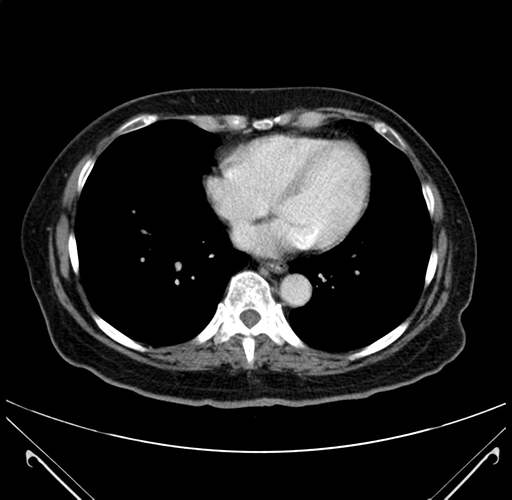

Pre-Chemo: Axial Venous